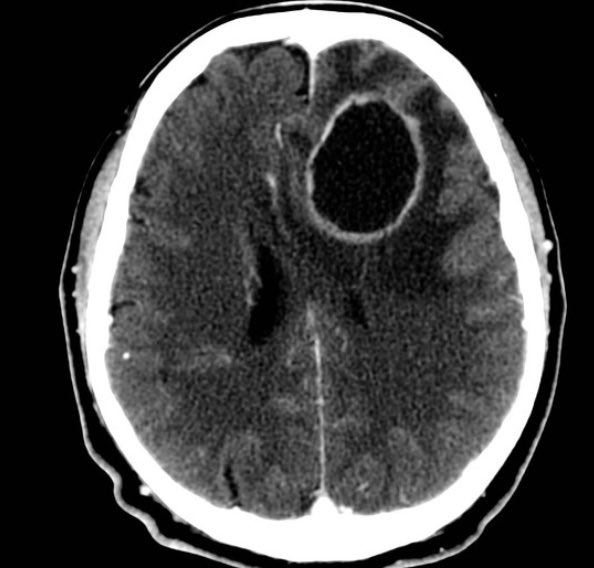

▫️Epidural hematoma🩸🧠

✳️Biconvex (Lens shape) that don’t cross suture lines